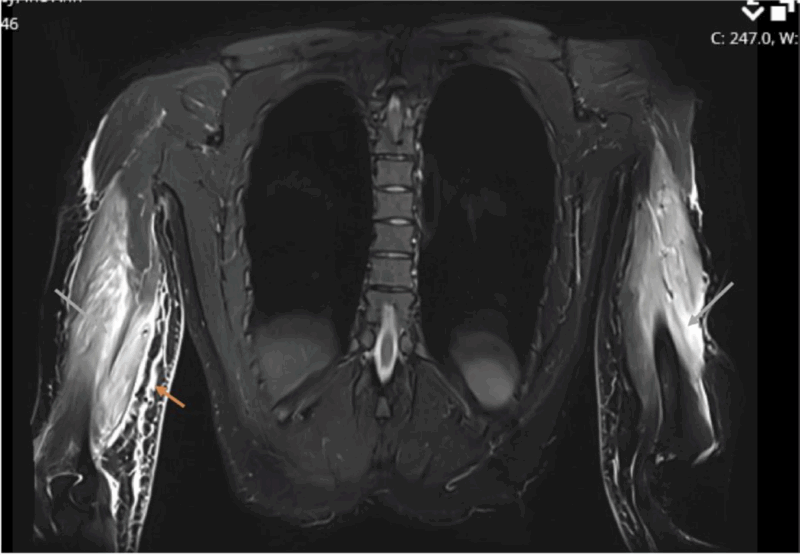

損傷した上腕三頭筋が白く写っています.

大腿の内側の筋肉(内転筋)が炎症を生じた結果, 白く写っています.

16時半過ぎにMRIが撮れたので, 確認しました. 腕にできた腫瘤の患者さんで, 腫瘍が疑われて紹介されてこられました. MRIでは, 明らかな腫瘍のような病変は認められず, 腕の筋肉(上腕三頭筋)が部分的に切れた状態(筋部分断裂:いわゆる肉離れ)と診断しました. ただし, 3年前に大学病院で甲状腺癌に対して甲状腺を切り取る手術が行われていました. 癌が筋肉の中に転移している状態も否定できません. 外来で経過を見て, 通常の筋部分断裂後の経過と異なる場合には, さらに検査を行うことを説明して, 次回の予約を入れました.